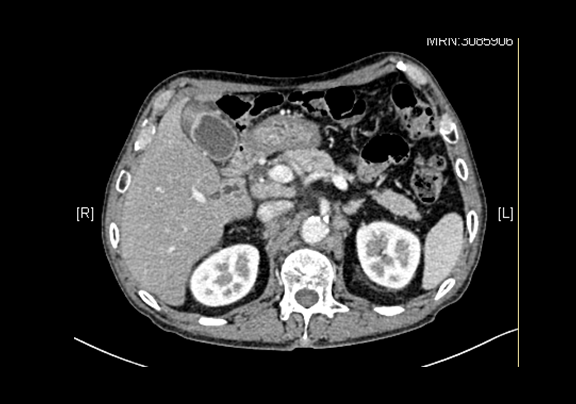

下腹部增强CT示:胆囊壁局限性不均匀增厚;疑似胆囊Ca;肝内外胆管扩张、肝左内叶类圆低密度影,感染性病变可能性大,肝左内叶类圆低密度影,暂不除外转移。

术前CT检查:

动脉期

静脉期